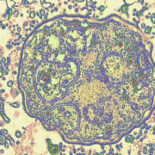

El curioso caso del hombre que venció al VIH

La historia comenzó cuando el paciente, ya enfermo de sida, desarrolló una leucemia.A pesar del tratamiento a base de radioterapia y quimioterapia, la solución pasaba inevitablemente por un trasplante de médula. Y en este punto su doctor, Gero Hütter, de la Charité Medical University de Berlín, tuvo una idea.De entre los 80 donantes compatibles con el paciente que vivían en Alemania, el galeno eligió la muestra 61, que pertenecía a un individuo con una mutación genética, heredada de sus padres, que le hace inmune a casi todas las cepas del VIH.